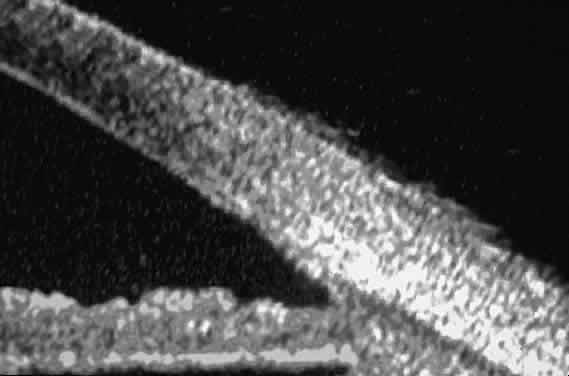

UBM has been used to evaluate various solid epibulbar masses, including limbal dermoids, squamous cell carcinomas of the conjunctiva, conjunctival cysts, and episcleral extensions of ciliary bodyneoplasms (Fig. 28).3 A limbal dermoid appears on UBM as an intensely sonoreflective mass involving and replacing the corneal and scleral stroma at the limbus (see Fig. 28A). The UBM images can reveal whether the lesion involves only partial thickness or full thickness of the stroma and can thereby aid in surgical planning. An acquired epibulbar neoplasm, such as squamous cell carcinoma of the conjunctiva and its variants, typically appears on UBM as an irregular, abnormally sonoreflective epibulbar mass adjacent to normal conjunctiva (see Fig. 28B and C). UBM allows measurement of the lesion's thickness and determination of the presence or absence or intraocular invasion (see Fig. 28D). Extrascleral extension of a ciliary body melanoma can simulate a conjunctival melanoma in some cases. UBM of such eyes confirms the presence, character, and extent of the underlying ciliary body tumor and often reveals the route of access of the tumor to the surface by way of a scleral emissary canal (see Fig. 28D).14

Fig. 28. UBM features of epibulbar mass lesions. (A) Composite UBM image of limbal dermoid. Lesion is sonoreflective and appears to replace full-thickness limbal cornea and sclera. (B) Squamous cell carcinoma of conjunctiva without intraocular invasion. Mass appears as fusiform thickening of limbal conjunctiva. (C) Squamous cell carcinoma of conjunctiva with scleral invasion. Invaded sclera appears abnormally sonolucent and nonuniform in thickness. (D) Extrascleral extension of ciliary body melanoma by way of scleral vascular or neural foramen.